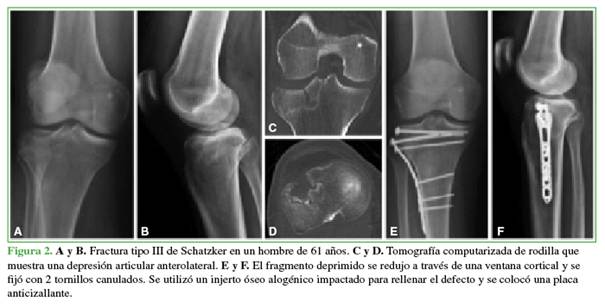

En el otro procedimiento, se restituyó la superficie articular con aloinjerto óseo impactado desde una ventana distal, se colocaron 2 tornillos canulados (de 4,5 o 6,5 mm) y luego se impactó y rellenó nuevamente con aloinjerto para ocupar el defecto metafisario (Figura 2).